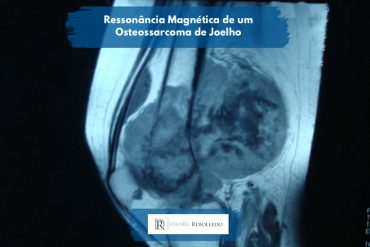

A Ressonância Magnética também é um ótimo exame. Ela avalia de forma mais detalhada o tamanho do tumor, seu tipo e em tumores de partes moles é o melhor exame para avaliação.

Câncer no joelho fotos